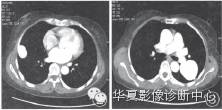

CT检查:肺窗示双肺纹理清晰,走行自然,肺野透光度可,双肺可见大小不等类圆形囊状影,边界清晰,增强扫描内可见对比剂充盈,并可见供血动脉(起自肺动脉)及引流静脉(汇人肺静脉),位于右肺者大小约为3.7 cm×2.8 cm×2.7 cm,位于左肺者大小约为6.6 cm×4.9 cm×5.0 cm,双肺门不大。纵隔窗示心影及大血管形态正常,纵隔内未见肿块及肿大淋巴结(图2~4)。CT诊断:双肺动静脉瘘。

图2,3增强扫描双肺团块状密度增高影明显强化,强化程度与主肺动脉及主动脉相一致